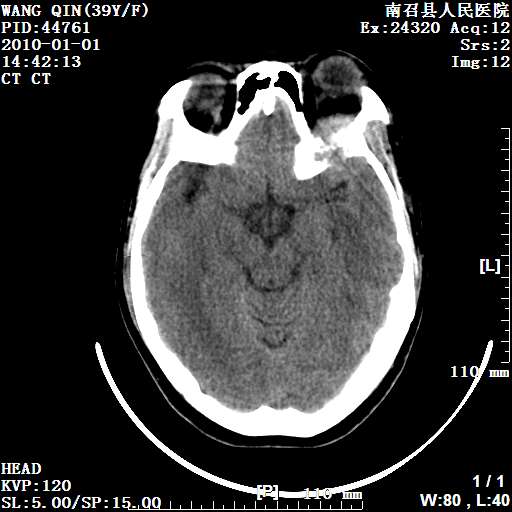

以下是引用随光逐影在2010-1-22 9:03:00的发言:[br]考虑左侧中颅窝(蝶骨翼区)脑膜瘤侵犯蝶骨翼并突入左侧眼眶。

以下是引用水过无痕在2010-1-22 14:55:00的发言:[br]一、定位:颅外占位;二、定性:恶性可能性大;三、组织来源:来源于左侧眼外直肌或其他部位;考虑为:横纹肌肉瘤>转移瘤>脑膜瘤.